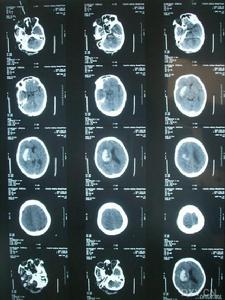

肌陣攣性小腦協調障礙腦部CT

雖然對RHS的認識已有70多年的歷史,但是目前對本病的認識還比較膚淺,還存在一些問題值得進一步探討:(1)RHS這一名稱並未被普遍認可,其恰當的命名、分類及與其他臨床表現類似的疾病相鑑別上還存在許多問題;(2)肌陣攣性癲癇和小腦性共濟失調的關係及其解剖和病理生理學機制尚不清楚;(3)運動性肌陣攣的存在使人們很難評價小腦功能;(4)原發性癲癇和肌陣攣的病人多年後出現共濟失調,是否與抗癲癇藥有關;(5)區分肌陣攣和非癲癇性生理性肌陣攣從臨床和電生理上是十分困難的;(6)RHS與PME之間的關係很混亂,它們既不能完全等同,但又有重疊。